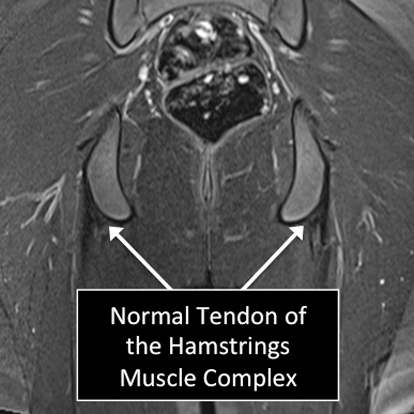

Hip MRI examinations showing normal (top) and abnormal (bottom) tendon of the Hamstrings Muscle Complex.

Why Translational MRI of the hip?

- In the hip, as in many other parts of the body there are certain structures that can’t be seen (they look black or dark) with the standard MRI.

- There are new “software” programs that allow us to see structures with different contrast (bright versus dark).

- Some of these “invisible” or dark structures are unique to the hip (acetabular labrum) and others are found in other parts of the body (e.g. cartilage, ligaments, tendons, cortical bone).